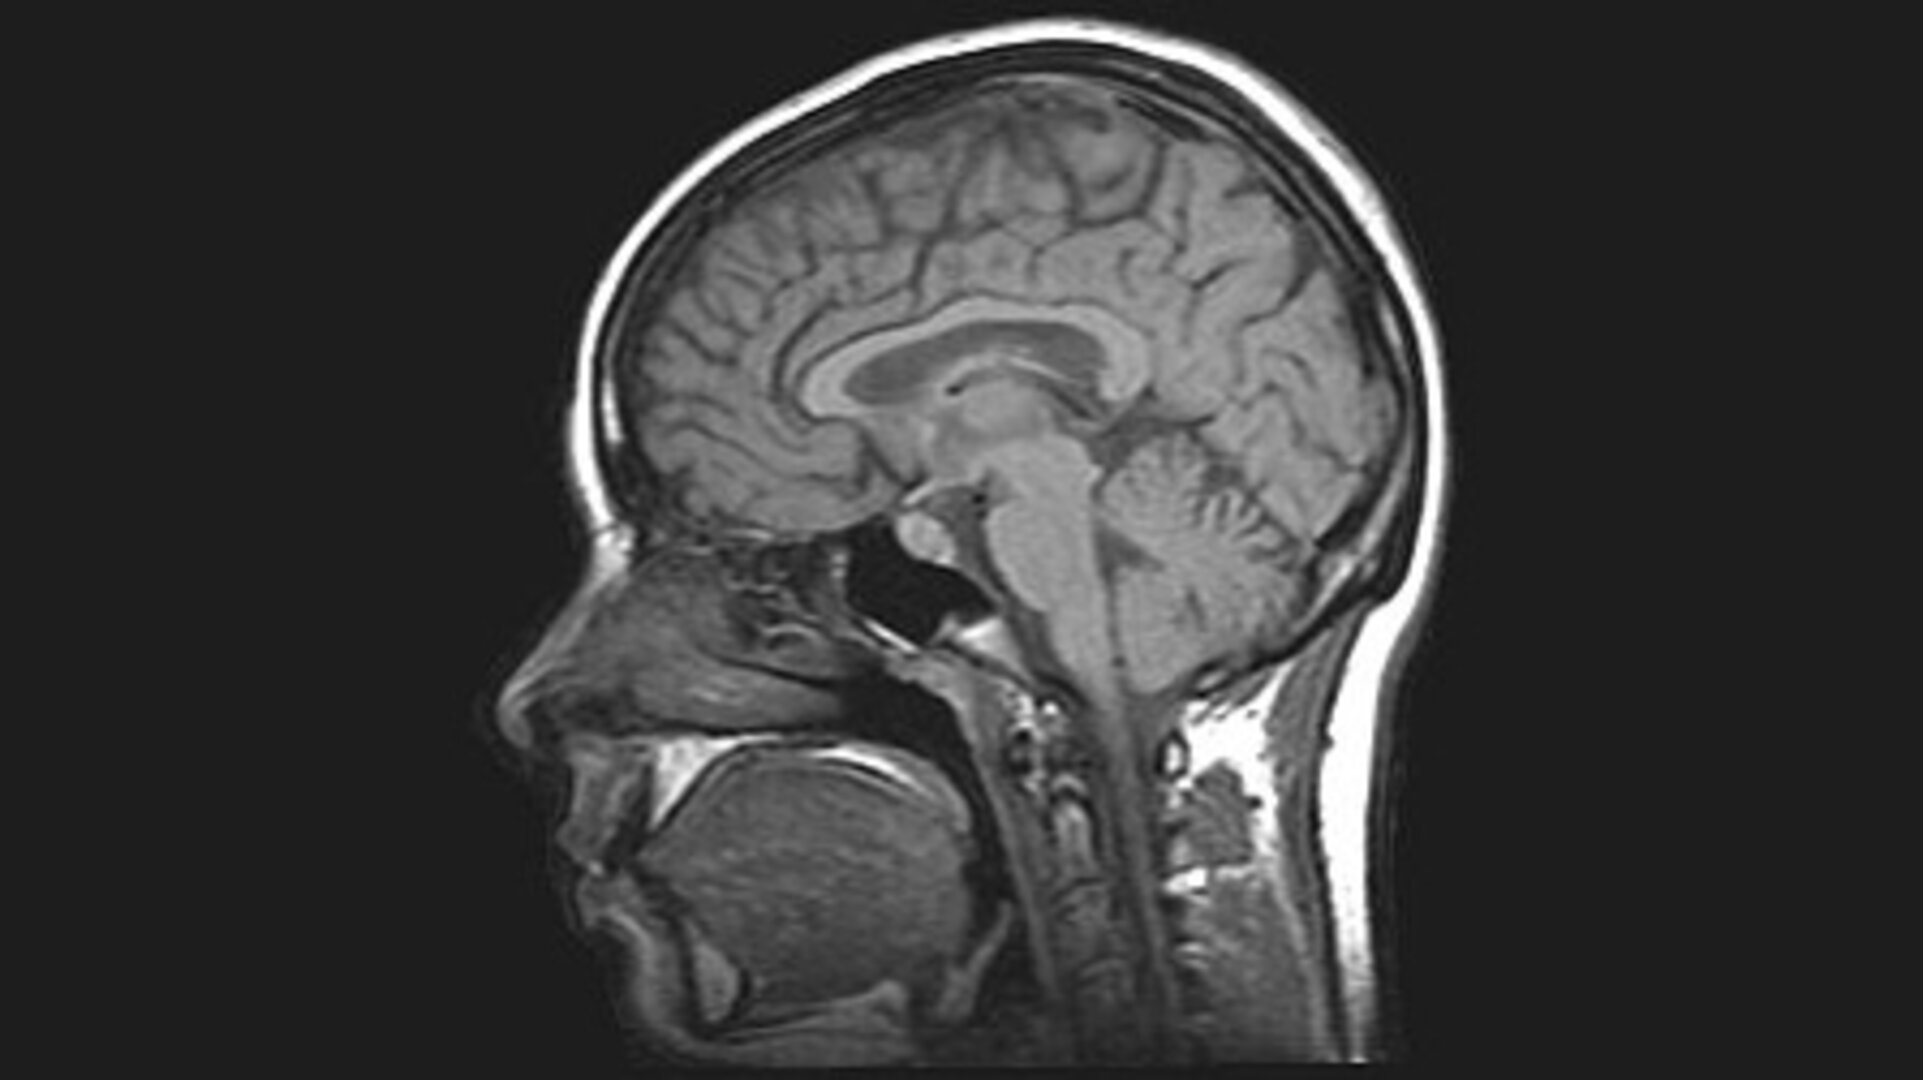

MRI Scan Image Of Brain | Regional Medical Imaging

www.rmipc.net

www.rmipc.net

brain mri imaging

Human Brain MRI Scan Stock Photo. Image Of Accident, Cancer - 37215148

www.dreamstime.com

www.dreamstime.com

mri brain scan human stock vertical section royalty mr

ESA - MRI Brain Scan

www.esa.int

www.esa.int

mri brain scan alzheimer using space imaging human software scans wikipedia identifying esa researchers hypothalamus applications pillars medical wiki thalamus